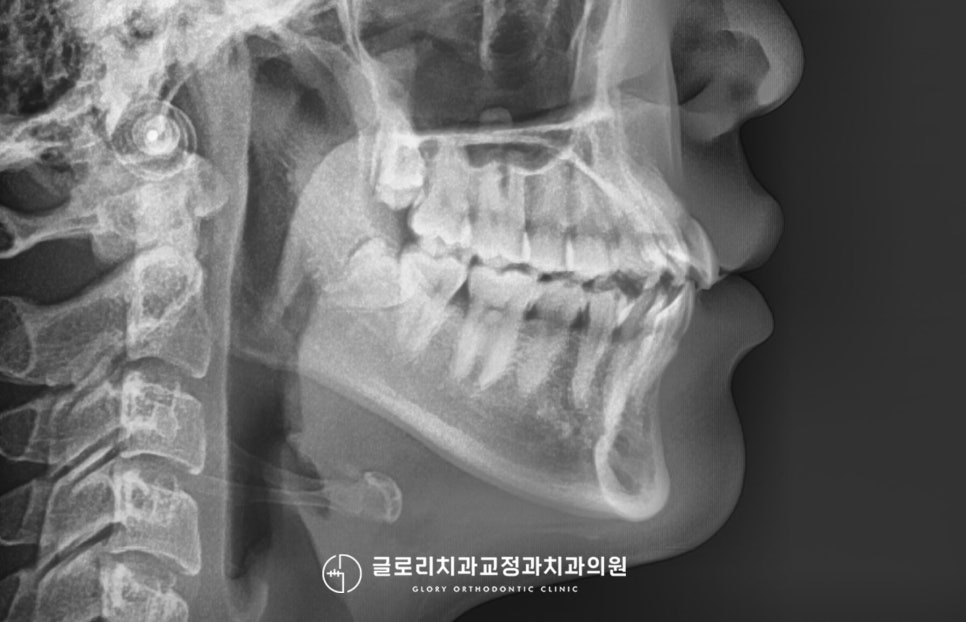

물론 개인마다 가진 구강 구조부터

턱뼈의 위치가 달라 모두 같은 조건으로

그렇기 때문에 신내동 치과 에서는

개인 맞춤별로 꼼꼼한 진단을 시행해

알맞은 치료 방법을 설계하고 있는데요.

치료를 시작하기 전

전체 교합이 모두 잘 맞으며,

일부만 수정이 필요할 경우에는

앞니 부분교정을 시행할 수 있습니다.